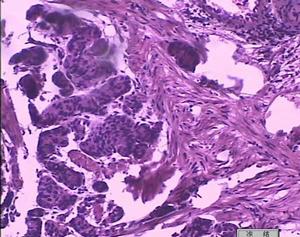

食管賁門失弛緩症2.食管本身的併發症:本病可繼發食管炎、食管黏膜糜爛、潰瘍和出血、壓出型憩室、食管-氣管瘺、自發性食管破裂和食管癌等。本病食管癌的並發率為0.3%~20%。綜合1908~1975年間文獻報告的5235例食管賁門失弛緩症,並發食管癌者173例,平均發生率為3.3%,顯著高於一般人群,應予重視。